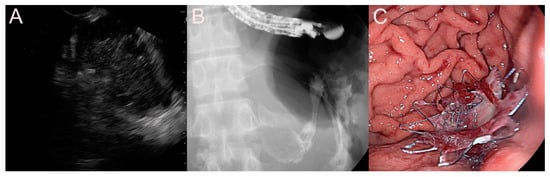

2.1. Stent for EUS-Guided Peripancreatic Fluid Collection (PFC) Drainage

2.1.1. Use of the Plastic Stent

2.1.2. Use of the Self-Expandable Metal Stent (SEMS)

2.1.3. Use of the Lumen-Apposing Metal Stent (LAMS)